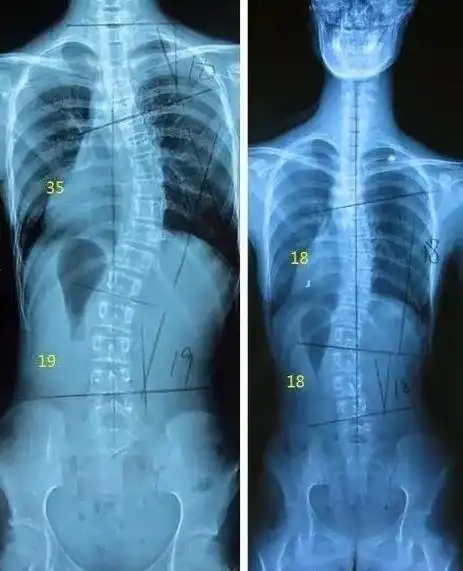

青少年脊柱侧弯自我筛查——湘潭市中医医院康复医学科爱心义诊活动